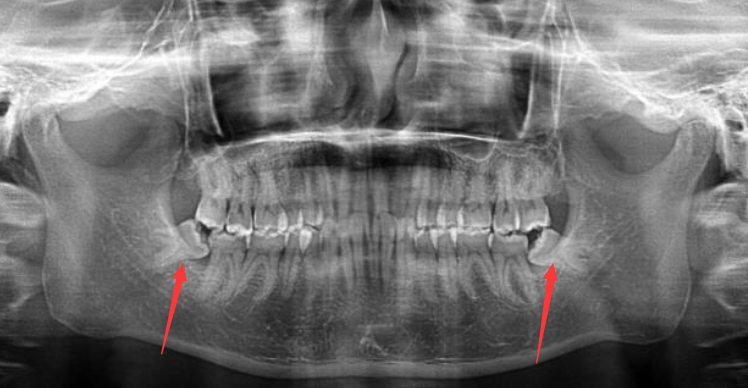

下面是我的牙齿全景图,箭头标的就是下面的两颗阻生齿,死死地顶住旁边正常的牙齿。上下一共四颗,长边的两颗长的还挺端正,先不考虑拔掉。